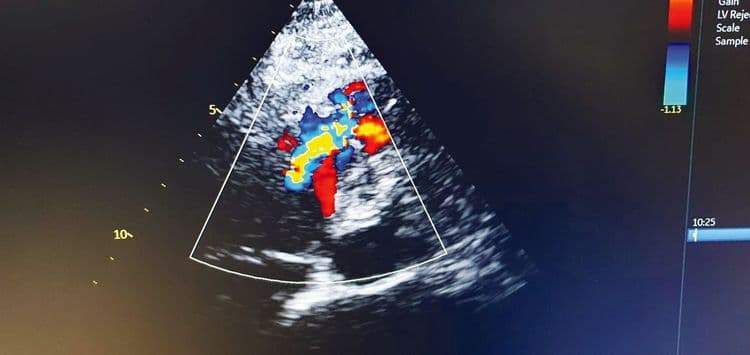

W Kociewskim Centrum Zdrowia w Starogardzie Gdańskim wykonano kolejny skomplikowany i rzadko spotykany zabieg kardiologiczny – przezskórne zamknięcie pozawałowego ubytku w przegrodzie międzykomorowej (VSD).

To wyjątkowa procedura stosowana w ciężkich powikłaniach po zawale serca. Jej powodzenie wymaga współpracy specjalistów z różnych dziedzin: kardiologii inwazyjnej, echokardiografii i intensywnej opieki medycznej.

Zespół w składzie: dr n. med. Maciej Chojnicki, prof. Marek Koziński, lek. Piotr Buda, lek. Agata Polańska-Szczap, Ewa Erdmann, Lidia Trzos, Katarzyna Kościerska oraz lek. Magdalena Tulińska wykonał zabieg z pełnym powodzeniem. Stan pacjentki uległ poprawie, a jej parametry echokardiograficzne systematycznie się stabilizują.